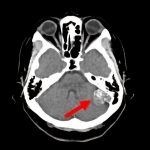

断層撮影

摘出 後